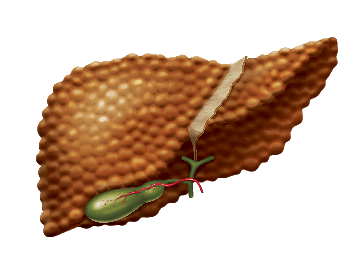

Як відбувається пошкодження гепатоцитів?

В основі пошкодження гепатоцитів лежить запалення, яке може привести до загибелі клітин печінки (цитолизу)

1 надмірне накопичення

жиру (стеатоз) 2 надмірне утворення

вільних радикалів 3 запалення 4 пошкодження

гепатоцита 5 формування рубцевої

тканини (фіброз)

Як розвивається процес руйнування печінки?

Основні стадії розвитку

захворювань печінки

Основні стадії

розвитку захворювань

печінки

накопичення

жиру

в гепатоцитах

надмірне

освіта

вільних

радикалів

і розвиток

запалення

загибель

гепатоцитів

і їх заміщення

рубцевої

тканиною

необоротне

порушення

структури

і функцій

печінки